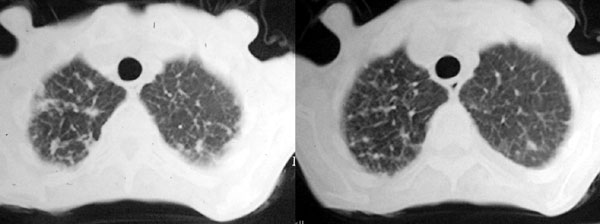

f 76 间断咳嗽 咳痰1年余 发热不明显 身体削瘦

征象:

1、右肺中叶近肺门区可见一空洞样病灶,内壁不规则,有与邻近支气管相通的征象,其外侧大片肺组织软组织状实变,余肺可见散在点、片絮状密度增高影,肺纹理可见明显增粗及串珠样改变;

2、纵隔气管前、隆突下、内乳组、心右前间隙以及右侧腋窝内均可见肿大的淋巴结节;

3、右侧胸膜增厚粘连,胸腔少量积液征像;

4、其它征像略。

诊断意见:

1、右侧中央型(空洞性)肺癌并双肺受累(包括转移、阻塞性炎症、癌性淋巴管炎);纵隔、右侧腋窝内淋巴结肿大、转移;右侧胸膜增厚粘连,胸腔少量积液;

2、双上肺陈旧性结核。

3、慢性支气管炎、肺气肿。